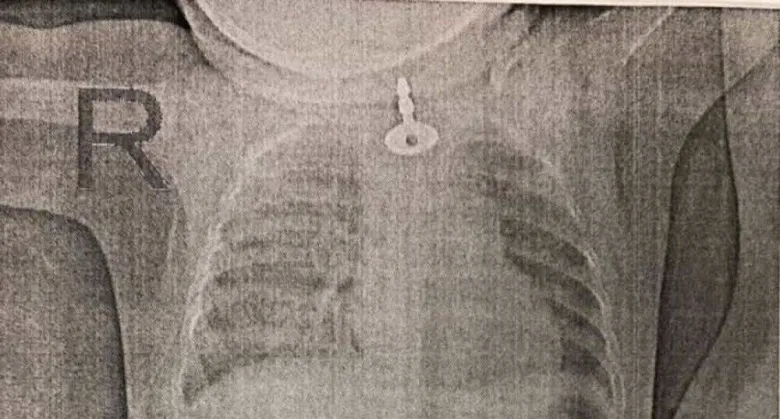

Նովոռոսիյսկից 11-ամսական աղջկա կերակրափողում բանալի էր խցանվել. Վիրահատությունը կատարել է հայազգի բժիշկը

Նովոռոսիյսկից 11-ամսական աղջկա կերակրափողում բանալի էր խցանվել. այն դուրս բերելու համար ստիպված էին վիրահատություն անցկացնել, որը կատարել է № 1 քաղաքային հիվանդանոցի բժիշկ-էնդոսկոպաբան Դավիթ Շահինյանը:

Ինչպես հայտնում է «Новороссийский рабочий» պարբերականը, աղջկան հիվանդանոց են բերել ուշ երեկոյան, եւ նա իրեն անհանգիստ էր պահում, ամբողջ ժամանակ ձեռքը տանում էր կոկորդին: Ռենտգենով նրա կերակրափողում օտար մարմին է հայտնաբերվել, և այն դուրս բերելու համար ստիպված էին անցկացնել էնդոսկոպիկ վիրահատություն

Վիրահատությունը տեւել է շուրջ 30 րոպե: Բժիշկը ստիպված էր բանալին նախ իջեցնել փոքրիկ պացիենտի ստամոքս, որ այն բռնելը հարմար լինի: Բայց բանալին դուրս բերելը հեշտ չէր, քանի որ կերակրափողում կան նեղացումների երեք գոտիներ, եւ վերջինով բանալին ոչ մի կերպ չէր անցնում՝ ցած էր սահում: Այն պետք էր դուրս բերել խնամքով՝ կերակրափողը չվնասելու համար: